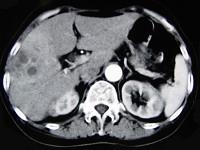

问题 女,66岁,右上腹痛,发热伴有黄疸两月余,消瘦、纳差,影像检查如图,最可能的诊断是 ( )

选项 A、肝内胆管细胞癌 B、胆囊癌及原发性肝癌 C、胆囊结石及肝血管瘤 D、胆囊癌肝转移 E、胆囊结石及脂肪肝

答案 D